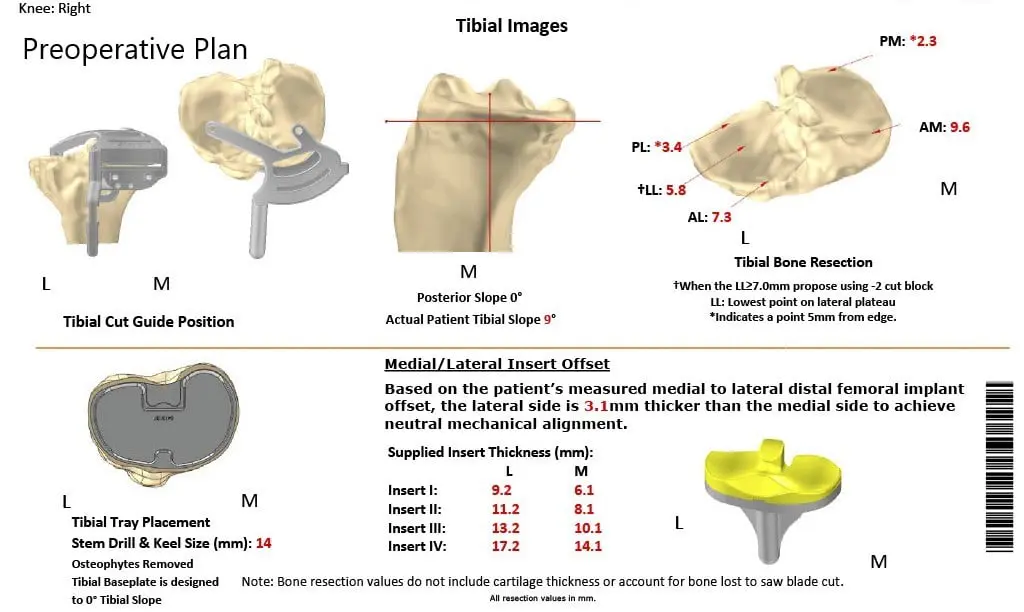

A preoperative CT scan of the right knee with the hip and ankle was taken several weeks prior to the procedure. This aided in a better understanding of the patient’s knee anatomy and biomechanics. The data was used to construct a patient-specific implant. Disposable cutting blocks were constructed for creating bone resection as outlined in a preoperative surgical plan.

Complete Orthopedics patient-specific surgical plan for a customized total knee replacement in a 58-year-old female with arthritis.

Complete Orthopedics patient-specific surgical plan for a customized total knee replacement in a 58-year-old female with arthritis (scan 2)

A preoperative surgical plan outlining the bone cuts and femoral offsets